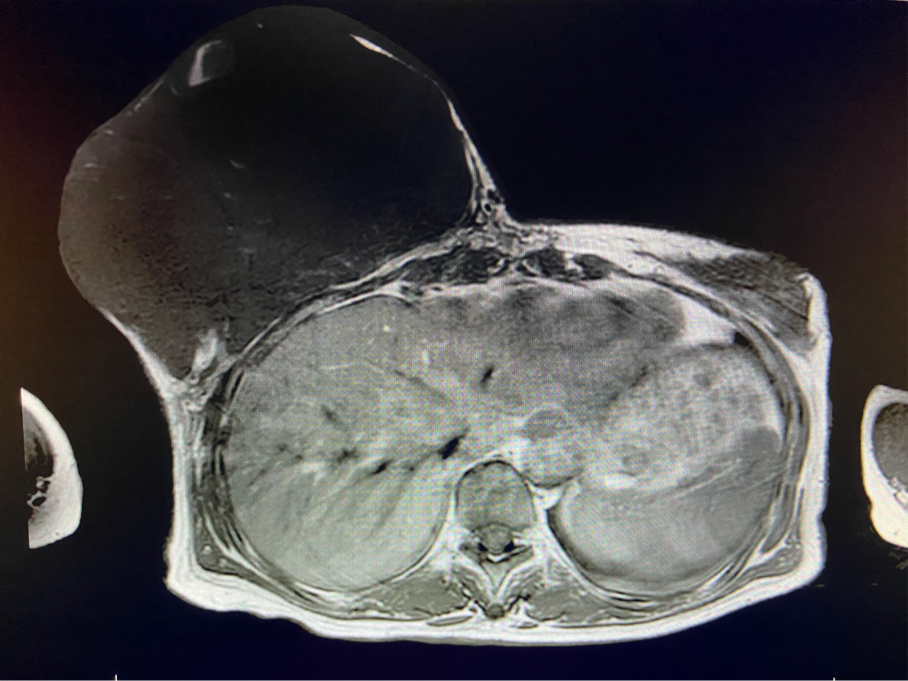

2周前,王女士的右乳外下方皮膚破潰,伴大量滲液,還發(fā)出陣陣惡臭。經(jīng)多方打聽,王女士從外地來到西安國際醫(yī)學中心醫(yī)院甲乳外科劉曉敏主任處就診。入院后,迅速完善了一系列相關術前檢查:王女士的雙乳外形不對稱,右乳約22?20cm,皮膚水腫明顯并可見靜脈曲張。右乳外下象限皮膚可見局部破潰,創(chuàng)面有3處,共約6?4cm大小,創(chuàng)面呈暗紅色,伴有血性滲出及惡臭,局部皮膚溫度升高。右側腋窩可觸及腫大淋巴結。

該患者右乳巨大腫物術前初步考慮乳腺葉狀腫瘤可能,因腫瘤太大,幾乎遍及整個右側乳房,為保證“無瘤原則”,術中切除范圍位置未知,極有可能出現(xiàn)皮瓣缺損。于是,經(jīng)過和整形醫(yī)院郭樹忠院長、整形外科王愛武主任的討論,提供了兩種手術方式,一是創(chuàng)面修復(植皮或轉移皮瓣修復創(chuàng)面),二是乳房再造,與患者及家屬溝通后,決定先解決腫物,3年病情不再復發(fā)后,可以再考慮乳房重建。

次日,在麻醉手術中心的默契配合下,劉曉敏主任團隊順利切除了重達5斤的病灶。后由王愛武主任及其團隊接手,仔細測量了剩余皮瓣后,由整形外科付德豐醫(yī)生對患者胸壁創(chuàng)面進行了縫合。術后,王女士傷口愈合良好,于近日順利出院,生活又恢復了正常。